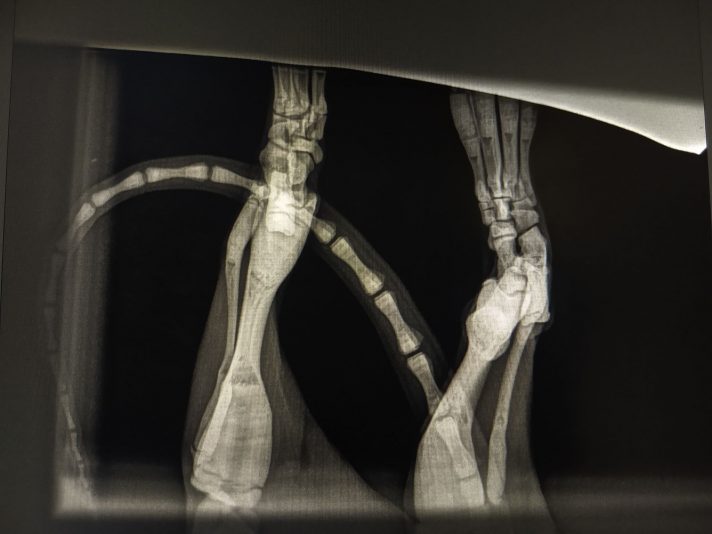

Signalement: Kattin intact van 7m, Europese Korthaar

Anamnese: Enkele weken geleden reeds klachten van manken op achterpoot en gezwollen tarsus. Was de kleinste van het nest en groeide moeilijk. Sinds verhuis erg stil en zit veel minder leven in. Eten, drinken, urineren en defeceren nog normaal.

Klinisch onderzoek: rustig maar alert. HF…